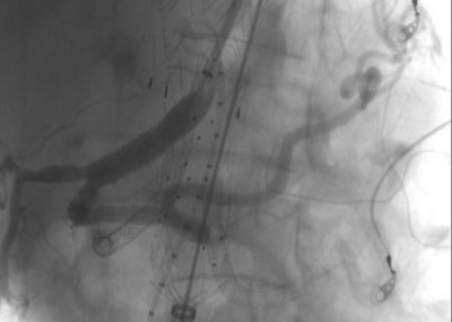

Di recente la U.O.C. Chirurgia Vascolare del Grande Ospedale Metropolitano di Reggio Calabria ha eseguito con successo un trattamento di elevata complessità su un paziente con un voluminoso aneurisma toraco-addominale (7 cm di diametro).

L’aneurisma toracico è stato trattato con un approccio endovascolare, mediante il posizionamento di endoprotesi; successivamente è stata posizionata un’endoprotesi ramificata per i vasi viscerali ed una terza endoprotesi aorto-bisiliaca. Il decorso post-operatorio è stato ottimale: il paziente non ha avuto complicanze ed è stato dimesso al proprio domicilio in buone condizioni di salute.